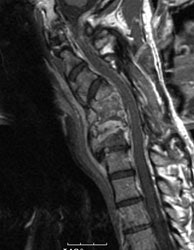

Cervical spine discitis and osteomyelitis: The case below is an example of the decreased sensitivity of In-111 WBC imaging for spinal infection. The MR images show abnormal disc enhancement at the C6-7 level consistent with discitis and enhancement of the C7 vertebral body consistent with osteomyelitis (white arrows). Post-gadolinium images are on the left. An In-111 WBC and Tc99m-Sulfur colloid exam in the same patient demonstrates a photopenic defect (black arrows) corresponding to the area of infection confirmed on the MR exam (white blood cell images are on the left). A defect on Tc-sulfur colloid imaging is seen with osseous infection due to marrow infiltration with inflammatory cells and edema which obstructs small arterioles. Click images to enlarge. |